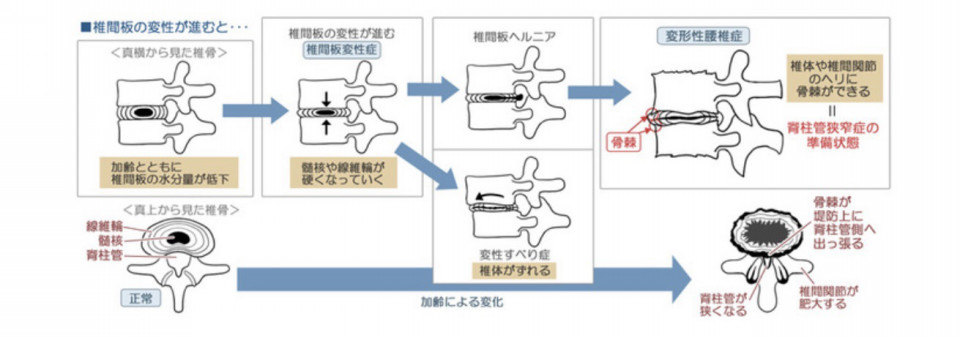

つまり整体が必要ないという話なんですが、 この椎間板の損傷を繰り返すとだんだん椎間板の水分量が減って椎間板の高さが低くなります。

椎間板の高さが減ることにより神経根の通り道が狭くなり腰部脊柱管狭窄症(足に痛みが出たり、痺れ、力が入らない)の原因になりますので再発を繰り返さないことが大切です。 椎間板は軟骨成分です。半月板と一緒で再生しないのでいかに痛めないかが重要です。

なぜかと言うと大概のヘルニアは3〜6ヶ月で飛び出た髄核(椎間板の中身)が神経を圧迫して脚に痛みや痺れを出しますが、その髄核を白血球が貪食(白血球が髄核を食べる)します。

次第に神経圧迫が取れて下肢の症状が消えます。

椎間板は軟骨成分なのである程度にしか再生はしません。

何度も急性腰痛を繰り返すと椎間板を痛めます。その椎間板は水分を失い高さがなくなり、低い椎間板になります。その後椎間板は柱の役割を失い後ろにあります。神経の通り道などが狭くなり、脊柱管狭窄症へ移行します。

・脊柱管狭窄症へ移行する。